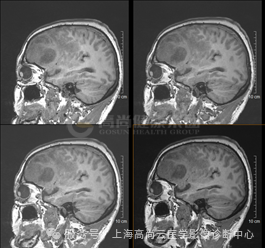

T1WI

T1WI 增强

左额叶见不规则团块状异常信号影,边界欠清,大部分 T1WI 呈稍低、低信号,T2WI 及 T2 FLAIR 呈等稍高信号,内见点片状低信号,DWI 呈高信号,相应区域 ADC 呈稍低信号,ADC 值约 0.793 ×10-3 mm2/s,最大横截面大小约 44 mm×55 mm,病灶后部 T1WI 呈低信号,T2WI 呈高低混杂信号,FLAIR 呈稍低等混杂信号,SWI 呈明显低信号,DWI 以低信号为主,病灶周围见大片水肿信号影环绕,邻近侧脑室明显受压,左额部中线结构略右偏,增强后病灶呈明显不均匀强化,内可见不规则无强化坏死区,强化区域灌注扫描 CBF 增高,MRS 显示局部 Cho 峰明显升高,NAA 峰明显升高,Cho/NAA 比值约 87.02,出现 Lip 峰及 LAC 峰。3D T1WI 增强显示左侧额叶病灶邻近脑膜增厚强化;另外右侧颞窝底部可见小条状强化灶。

高级别胶质瘤(4 级)